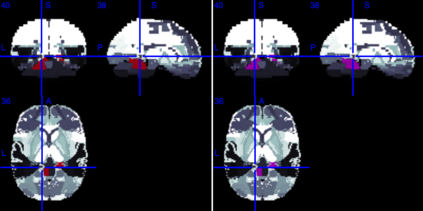

In this paper, we introduce a new Bayesian approach for analyzing task fMRI data that simultaneously detects activation signatures and background connectivity. Our modeling involves a new hybrid tensor spatial-temporal basis strategy that enables scalable computing yet captures nearby and distant intervoxel correlation and long-memory temporal correlation. The spatial basis involves a composite hybrid transform with two levels: the first accounts for within-ROI correlation, and second between-ROI distant correlation. We demonstrate in simulations how our basis space regression modeling strategy increases sensitivity for identifying activation signatures, partly driven by the induced background connectivity that itself can be summarized to reveal biological insights. This strategy leads to computationally scalable fully Bayesian inference at the voxel or ROI level that adjusts for multiple testing. We apply this model to Human Connectome Project data to reveal insights into brain activation patterns and background connectivity related to working memory tasks.